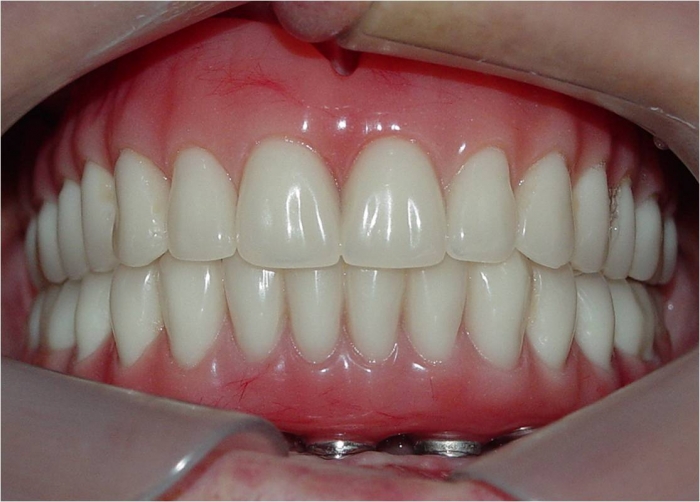

Sorriso final, do caso terminado em janeiro de 2014